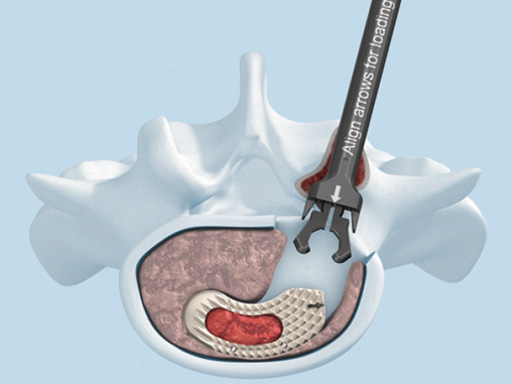

The new T-PAL system is an innovative minimally invasive surgical cage system designed to replace lumbar intervertebral discs and facilitate fusion of the adjacent vertebral bodies at vertebral levels L2/S1 in a transforaminal approach.

The development of T-PAL is a result of surgeons' feedback on the currently existing solutions for transforaminal lumbar fusion, in particular the request for improved instrumentation. It offers one main instrument the applicatorwhich can be used for both the trial positioning and the controlled placement of the implant in minimally invasive procedures. This instrument also features a security button to prevent premature implant disengagement.

The key new feature of T-PAL is the guidance rails on upper and lower surfaces of both the trial and final implants which guide the implant into the final position. This self-guidance feature places the implant exactly where the surgeon desires it in the disc space and consequently saves time and eliminates the need to constantly readjust the insertion angle. Unlike traditional rigid trials, the T-PAL trial implant pivots, allowing it to be placed in the same location as the implant.